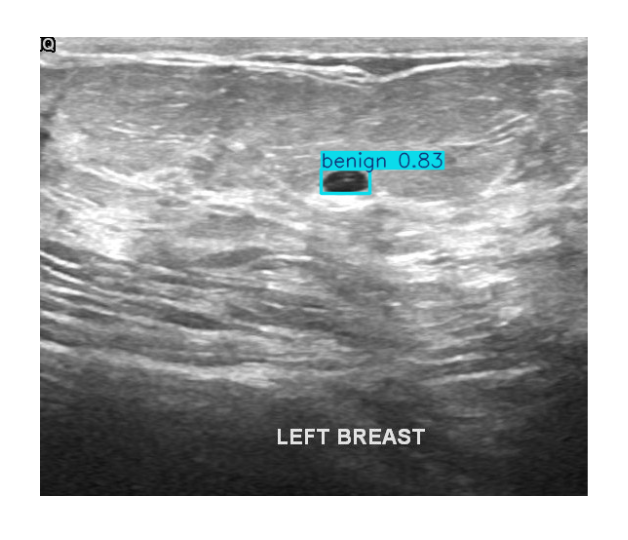

Supports multi-modal inputs including structured indicators, voice, dialogue, and imaging for comprehensive care.

Demo Cases